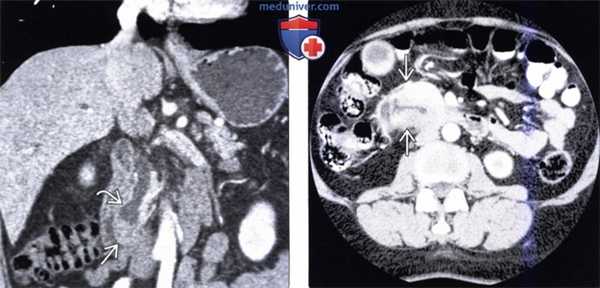

(Слева) На корональной КТ с контрастным усилением визуализируется полиповидное объемное образование (рак) в ампуле фатерова сосочка. Видна также часть билиарного стента ЕЕ. Изображения в корональной плоскости лучше всего позволяют визуализировать ампулу и оценить вероятное объемное образование.

(Справа) На корональной КТ с контрастным усилением визуализируется гиподенсное образование в ампуле, с нечеткими краями, вызывающие обструкцию общего желчного протока, при этом панкреатический проток расширен в незначительной степени. При оперативном вмешательстве был обнаружен рак ампулы фатерова сосочка.

(Слева) На корональной КТ с контрастным усилением (объемный рендеринг) определяется симптом «двойного протока» на фоне обструкции общего желчного и печеночного протоков, обусловленной полиповидным объемным образованием (рак) ампулы фатерова сосочка.

(Справа) На корональной КТ с контрастным усилением визуализируется дискретное объемное образование вокруг ампулы фатеровы сосочка, в которой находится билиарный стент. Рак ампулы сложно отличить от периампулярного рака двенадцатиперстной кишки методами визуализации, но, тем не менее, лечение в обоих случаях одинаково (операция Уиппла).

(Слева) На корональной КТ с контрастным усилением в ампуле фатерова сосочка визуализируется объемное образование округлой формы, с четкими контурами, приводящее к обструкции общего желчного протока. Рак ампулы практически всегда приводит к обструкции общего желчного протока, однако обструкция панкреатического протока возникает только в 50% случаев.

(Справа) На аксиальной КТ с контрастным усилением визуализируется инвазивная аденокарцинома ампулы фатерова сосочка, возникшая из ворсинчатой аденомы. Обратите внимание на циркулярное объемное образование большого размера (в виде «огрызка яблока») двенадцатиперстной кишки, располагающееся на границе ее второй и третьей части.